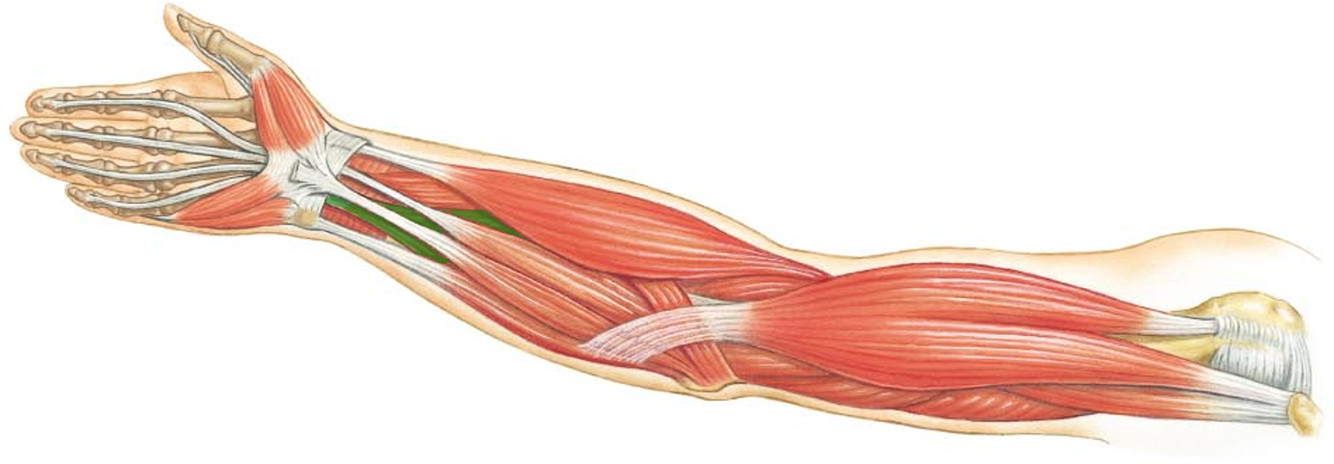

What is the innervation of this muscle?

Muscle - Pronator teres

Median nerve

What is the innervation of this muscle?

Muscle - Opponens pollicus

Median Nerve